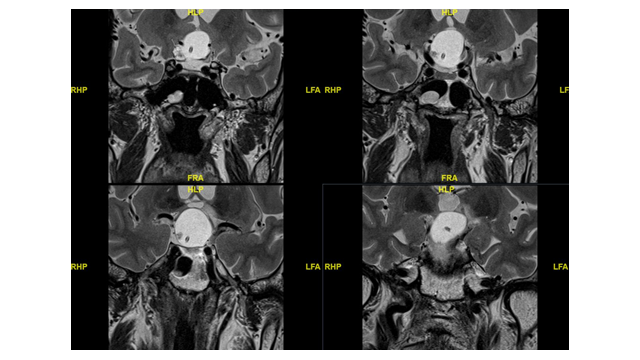

脑脊液外引流,交通性脑积水lp分流的新思路 .腰大池ommaya置入术一例

图片尺寸1200x1600